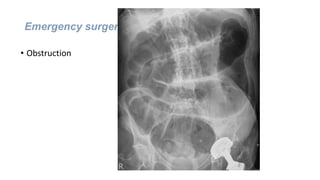

Emergency surgery

• Obstruction

Treatment

• Surgery - a Hartmann’s procedure

Stenting